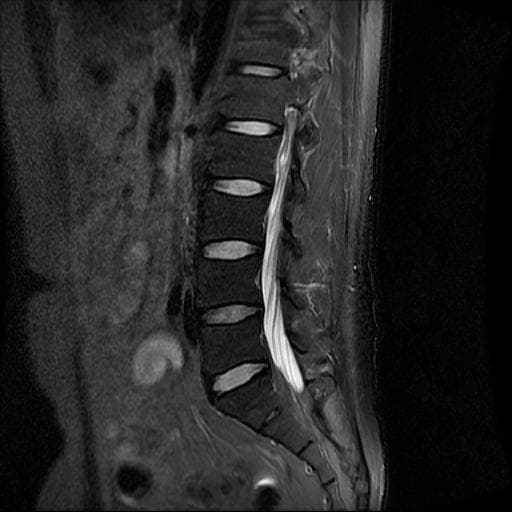

허리 MRI 디스크 상태 분석 부탁드립니다

검진 차 MRI찍었는데 분석 부탁드립니다.

건협에서는 관리해야 된다는데 디스크 협착이나 팽윤 등이 있는 상태인지 궁금합니다.

우선 현재로썬 사진만으론 판단을 하기에 제한이 되지만 사진상 디스크 상태는 심해보이지 않습니다.

요추부위의 하부 에서 약간의 팽윤이나 돌출로 의심해볼수 있는 정도이지만, 정확한 상태는 관련 전문의에게 진료시 문의를 하시는 것을 추천드립니다.